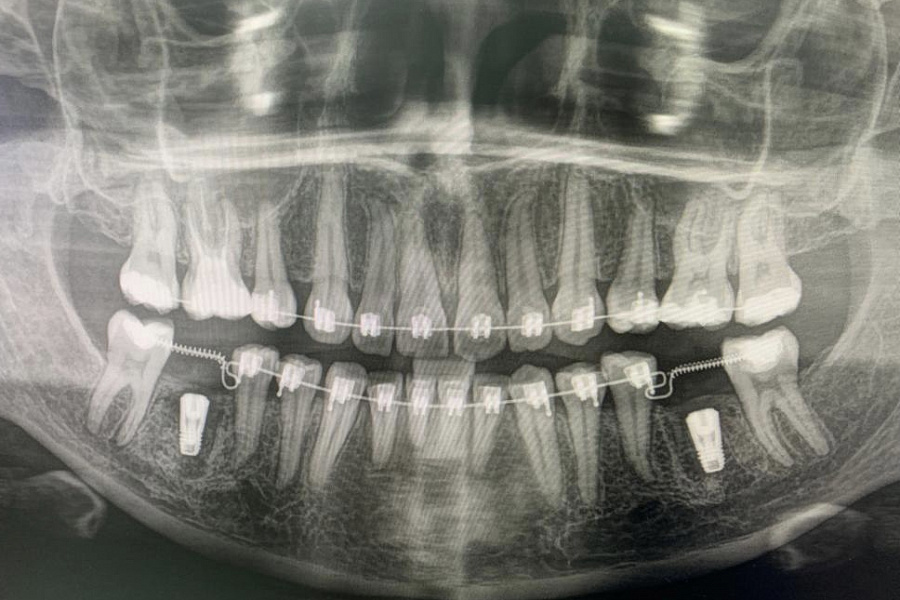

Пациентка начала ортодонтическое лечение и за 5 месяцев до окончания лечения ей удалили нижние шестерки и поставили импланты. За месяц до конца лечения установили формирователи десны. На момент снятия брекетов были сняты слепки под постоянные коронки на имплантатах.

В этом случае одновременно пациент закончил ортодонтическое, хирургическое и ортопедическое лечение. Что возможно только при одновременном подходе команды врачей.